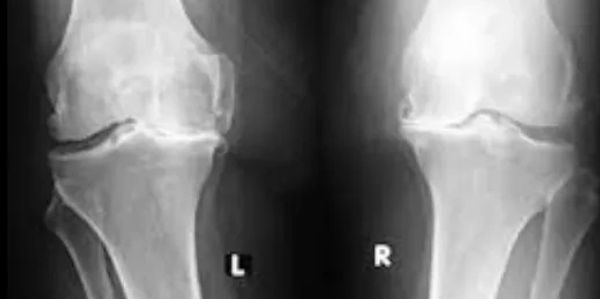

Diz ağrısının en yaygın sebeplerinden biri osteoartrozdur(eklem kireçlenmesi).Dizde olan osteoartroza ‘gonartroz’ denir. 50’li yaşlarla beraber en çok kadınlarda görülür.